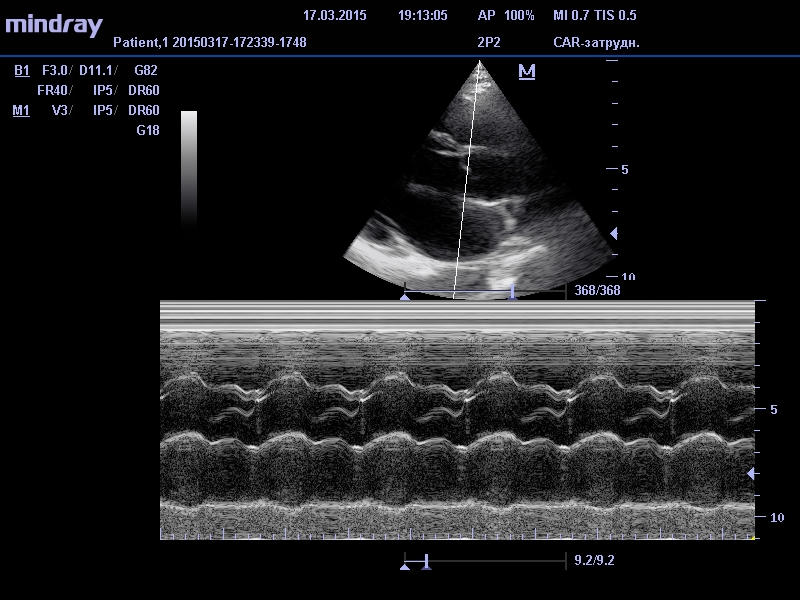

Смысл данной диагностической процедуры сводится к тому, что датчик посылает ультразвуковой сигнал (звуковая волна, которая не слышна человеческим ухом из-за своей невероятно высокой частоты) в область сердца. Из-за различной плотности тканей и расстояния ультразвуковые волны с различной скоростью отражаются от стенок сердца. Принимая обратный сигнал диагностический аппарат выстраивает картинку исследуемого органа.

Основными показателями, на которые обращают внимание специалисты-кардиологи при постановке диагноза больному, являются параметры правого и левого желудочка сердца, а также толщине перегородки между ними. Наиболее важные характеристики, это - масса сердечной мышцы, объем в состоянии покоя и объем в момент сокращения миокарда, количество выбрасываемой в результате сокращения крови. Эти данные специалист сравнивает с нормативами здорового человека, из чего делает выводы о состоянии здоровья кардиосистемы наблюдаемого пациента.